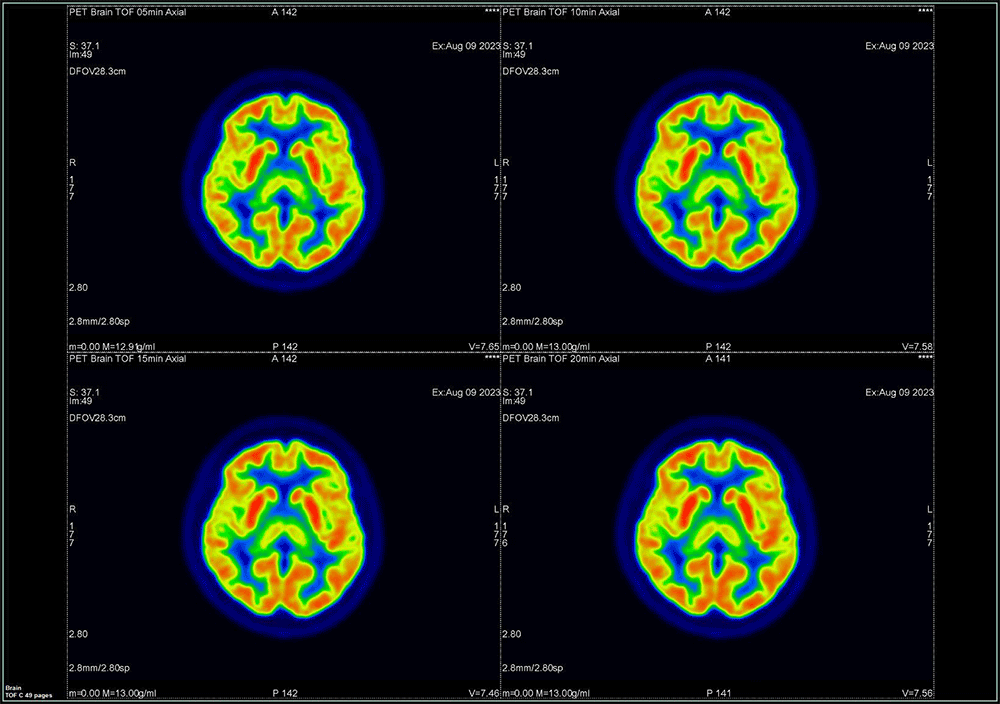

① OSEM法

OSEM画像をFig.5に示す。分解能の視覚評価においてマトリック数192以上では差を認めませんでした。

Fig5. 描出能の視覚評価 OSEM法